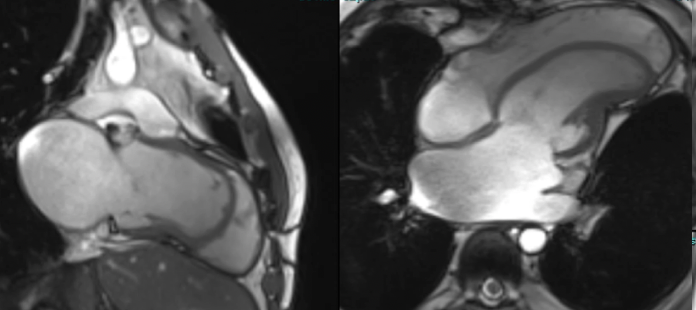

Isolated LV apical hypoplasia

An interesting case of a rare form of congenital cardiomyopathy.